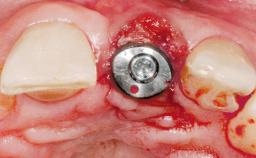

A 30-year-old female patient had lost tooth 21 and was referred to our clinic for consultation and treatment. Due to advanced apical infection, tooth 21 had been extracted two months earlier at another clinic and an acrylic-resin tooth had been bonded to the adjacent teeth. The patient desired implant treatment to avoid any damage to the adjacent natural teeth. While the patient had no history of any systemic disorder, she was a heavy smoker and exhibited medium to advanced periodontitis in the entire jaw. After the initial treatment to achieve a pocket probing depth of less than 4 mm and no bleeding on probing, a decrease in the height of the papillae mesial and distal to the extraction site and overall gingival recession were observed.

Type of Implants One-Piece|Reduced-Diameter

Soft Tissue Grafting Simultaneous

Retention Cemented, with meso-structure Cemented, with meso-structure

Provisional Implant-Supported Prosthesis Prosthodontic margin < 3 mm apical to mucosal margin Prosthodontic margin < 3 mm apical to mucosal margin